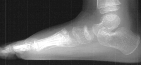

R.P. is a 3 year old girl who presented to the Orthopaedic Clinic with a complaint of left foot pain exacerbated by bearing weight. Four weeks prior to this visit, the patient's 4 year old sister had jumped onto her left foot during play resulting in pain and an antalgic gait. She had no pain in the left foot prior to this episode. She was evaluated at an outside emergency room where radiographs were remarkable only for radiodensity and collapse of the tarsal navicular. She was given a diagnosis of Kohler's disease and instructed to restrict her activities. The patient continued to have a limp and frequently complained of pain in her left foot, especially after activity. Her father brought her to the A.I. duPont Institute for evaluation.

Radiographs of the patient were obtained on her presentation to our clinic. These confirmed the finding of increased radiodensity of the navicular with a flattened appearance to the ossific nucleus. Furthermore they revealed increased density and callus formation in the proximal 1st through 4th metatarsals. This was consistent with multiple non-displaced fractures of the proximal metatarsals secondary to trauma. While Kohler's disease cannot be ruled out in this case, it is more likely that the patient had symptoms produced by her metatarsal fractures. The radiographic appearance of the tarsal navicular almost certainly preceded the acute traumatic event. Therefore, she probably had metatarsal fractures superimposed on irregular ossification of the tarsal navicular giving a clinical picture similar to Kohler's disease.